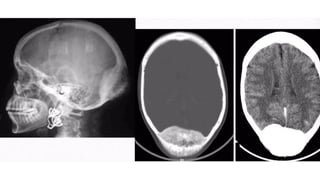

O s t e o m a

• Seen almost exclusively in bones formed in membrane

• • Slow growing, usually asymptomatic, found incidentally

• • L o c a t i o n - Paranasal sinus , Skull v a u l t , Mandible

• • Size

• • Varies, some > 2 . 5 cm

• • Types

• Ivory/dense

• • Lacks haversian system

• Spongy

• • Resembles normal bone

• Ivory osteomas appear very radio-dense

• Spongy osteomas may demonstrate central marrow

• Complications

• • Growth within PNS c a n cause mucocele

• • Growth from inner table of skull may produce raised intracranial pressure

• • Association - "Gardner syndrome"

• Multiple osteomas of skull, mandible and long bones

• > Familial adenomatous polyposis

Radiographic features

Ivory osteoma

Mandibular osteoma

Mandibular osteomas in Gardner syndrome